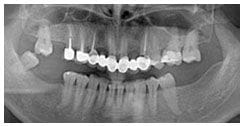

術前X光片